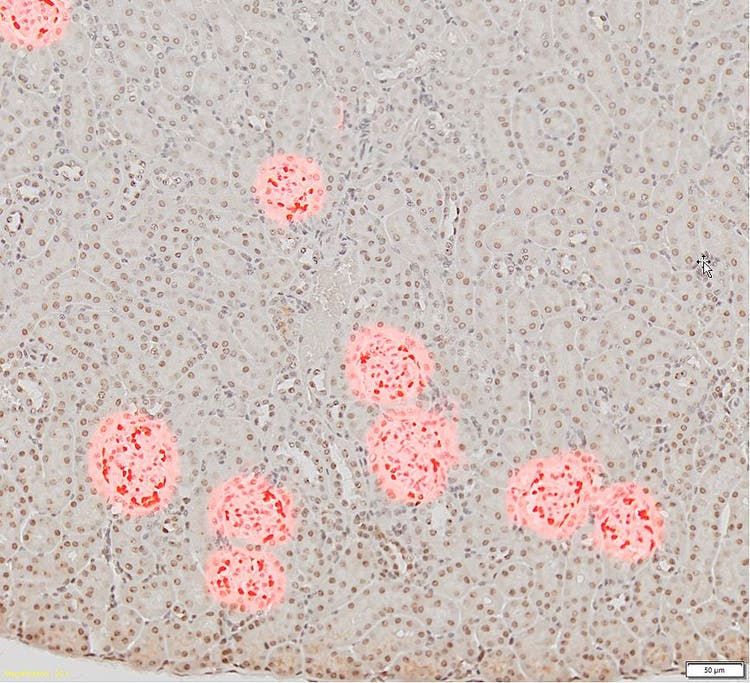

Objektträger (links) eines Nierengewebeschnitts bei 20-facher Vergrößerung mit dunkelbraun gefärbten Glomeruli und (rechts) bei 10-facher Vergrößerung. Es wird deutlich, dass die Glomeruli-Zellen mit der herkömmlichen Schwellenwertmethode (in rot) nicht von anderen Gewebezellen unterschieden werden können.

Bilder mit freundlicher Genehmigung von Zhenhua Miao, Principal Scientist bei ChemoCentryx, Inc. Mountain View, CA (USA)

Für die Analyse dieser Strukturen in gescannten Bildern werden die Glomeruli normalerweise manuell ausgewählt, was sehr zeitaufwändig ist. Mit herkömmlichen automatischen Segmentierungsmethoden, beispielsweise schwellenwertbasierten Algorithmen, ist es nicht möglich, ausschließlich Glomeruli zu erkennen (siehe oben).